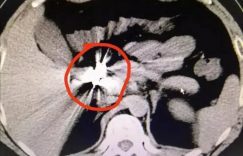

男生为何赌气吃一条金项链 得知什么原因竟然让医生崩溃?

原本医院消化内科的医生平日里就要见识各种被一不小心误吞进去的东西,想必应该说是见怪不怪了。但是近日浙大一院的一名病人所吞进去的东西,还真是让医生吓了一跳,而且这个病人还并不是误吞,而是自己吞下去的,这是怎么回事呢?